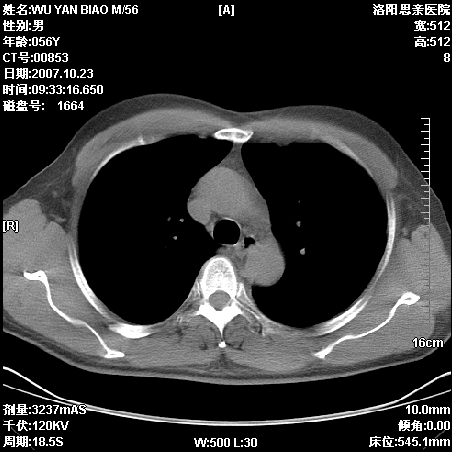

标题: CT10160:M56Y,体检发现,病人无不适,病人随访中 [打印本页]

标题: CT10160:M56Y,体检发现,病人无不适,病人随访中

后上纵隔占位,与肺交界清,宽基底附着脊柱,密度均匀,局部骨质无明确改变.

考虑;神经源性肿瘤,---起源交感n链?,不除外肠源性囊肿.

后纵隔神经原性肿瘤可能性大,孤立性胸膜间皮瘤待排.

1、病灶在后纵隔脊柱旁沟内,此处是神经原性肿瘤的好发部位

2、病灶边缘光滑整齐,更说明病灶来于纵隔,由于有胸膜的包裹所以才导致这么光滑的边缘

3、病灶内的密度均匀